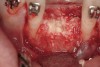

Figure 16  The edentulous anterior sextant. Portions of the facial bony wall remain in the maxillary left central and lateral incisor region. The long-standing abscess associated with tooth Nos. 7 and 8 has resulted in total loss of the bony plate in this area.

Figure 16